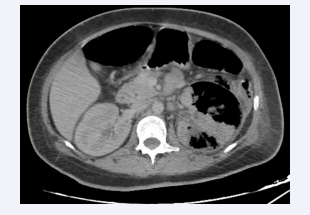

Axial section of an abdominal CT scan after intravenous  contrast injection at portal time, showing an enlarged right kidney with  diffuse “bear’s paw” calcific dilatation upstream of a pelvic coralliform  calculus, with air bubbles within the calyces and renal parenchyma. The  appearance is compatible with EPN on xanthogranulomatous APN class  2 according to Huang et al.

Figure 5: Axial section of an abdominal CT scan after intravenous contrast injection at portal time, showing an enlarged right kidney with diffuse “bear’s paw” calcific dilatation upstream of a pelvic coralliform calculus, with air bubbles within the calyces and renal parenchyma. The appearance is compatible with EPN on xanthogranulomatous APN class 2 according to Huang et al.